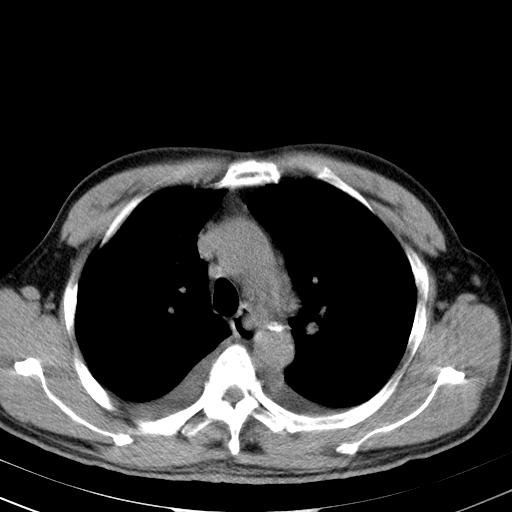

以下是引用zjzjr在2010-3-21 17:39:00的发言:[br]右下中心型肺癌并阻塞性肺炎/不张,纵膈淋巴结肿大,右侧大量胸腔积液,左侧少量胸腔积液

以下是引用zxl51642在2010-3-21 17:06:00的发言:[br]右下中心型肺癌并阻塞性肺炎/不张,纵膈淋巴结肿大,右侧大量胸腔积液,左侧少量胸腔积液,少量腹水。建议纤维支气管镜进一步检查。